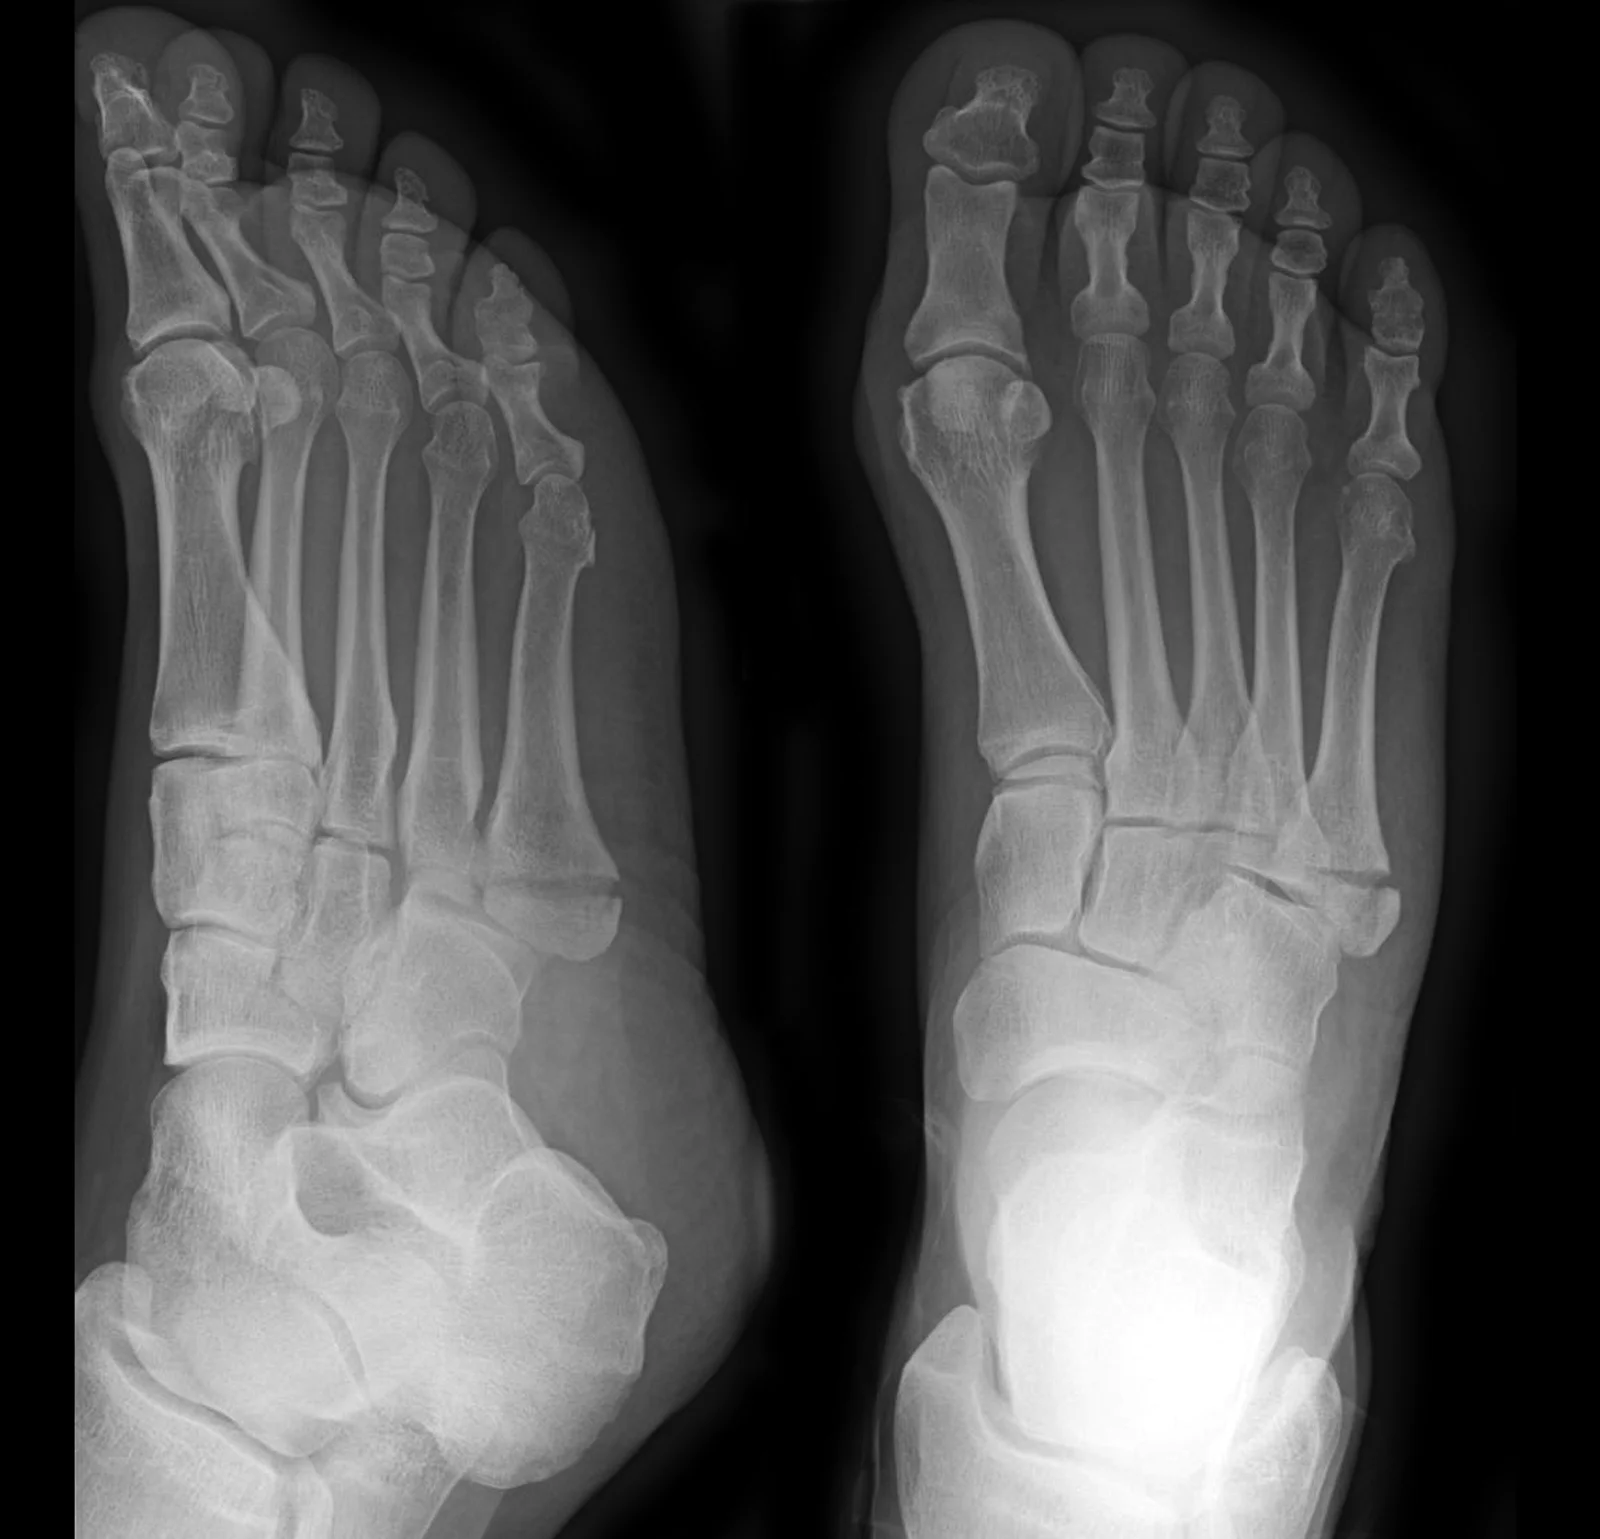

For pain relieve, ice and acetominophen can be helpful. Oblique radiograph of the foot shows a transverse avulsion fracture (arrow) of the 5th metatarsal bone with displacement and extension into. Foot fractures are among the most common foot injuries evaluated by primary care physicians. I feel only a little pain in my ankle from the. For a stress fracture of the foot, the best treatment is to give the foot time to heal by resting as much as possible.

In children, avulsion fractures that involve the growth plates also might require surgery. The most common problem is distinguishing this injury a fifth metatarsal avulsion fracture is a common injury that occurs when the foot is twisted awkwardly. I am almost 10 weeks out from a bad fall resulting in a 3°ankle sprain and a complete non displaced fracture at the base of the 5th metatarsal. Oblique radiograph of the foot shows a transverse avulsion fracture (arrow) of the 5th metatarsal bone with displacement and extension into. An avulsion fracture occurs when a tendon or ligament that is attached to the bone pulls a piece of the fractured bone off. Proximal fifth metatarsal fractures have different treatments depending on the location of the fracture. If you have been given a boot to wear. Questions and answers regarding fractures of the foot and ankle.

This article will review multiple foot avulsion fractures, their respective mechanisms of injury, clinical and radiographic presentations, and most. Fractures of the toes and forefoot are quite common. In children, avulsion fractures that involve the growth plates also might require surgery. These are very common and usually happen at the same time as a sprained ankle. Use the video or information below to you may walk on the foot as comfort allows but you may find it easier to walk on your heel in the early stages. Avulsion fracture at the base of the fifth metatarsal (insertion. With an avulsion fracture, an injury to the bone occurs near where the bone attaches to a tendon or ligament. An avulsion fracture to your foot or ankle may require a cast or walking boot. Questions and answers regarding fractures of the foot and ankle. Indications for conservative or operative treatment are discussed in detail. Feet are very vulnerable to slipping and twisting. Oblique radiograph of the foot shows a transverse avulsion fracture (arrow) of the 5th metatarsal bone with displacement and extension into. Avulsion fractures can happen anywhere in the body but are most common in the ankle, hip, finger, and foot.